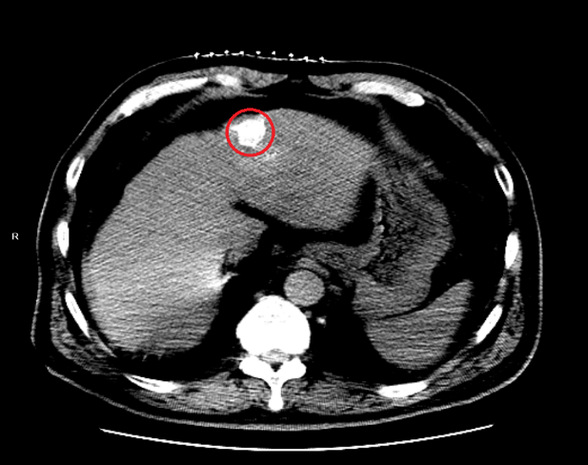

7月25日,67岁的患者周先生因头晕来到我院神经内科就诊检查,上腹部增强CT提示肝S4段占位性病变,大小为2.0*1.6cm。结合周先生既往有慢性肝炎及肝硬化病史,考虑为肝恶性肿瘤。患者及家属商议后,拒绝外科手术治疗。会诊时,我院介入科负责人莫庆国建议行TACE联合消融治疗。7月29日,我院介入科给予周先生TACE治疗。术后1月余,周先生再次来院复查,提示肝内病灶稳定,碘油沉积良好,欲给予肝内病灶消融治疗,但热消融风险较高,考虑到患者病灶靠近边缘,患者年龄等因素,莫庆国主任提出使用恢复更快、痛苦更小的肝癌冷冻消融术。

术前病灶